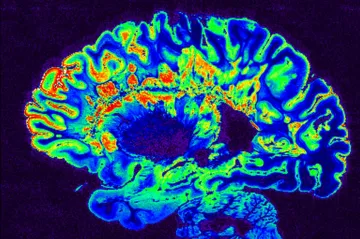

Obnovit řeč a schopnost komunikovat u pacientů s vážným motorickým postižením – třeba po poranění míchy – to zní jako zázrak. Ale ve skutečnosti je to cíl mozkového implantátu, který vyvíjí společnost Paradromics. Teď získala povolení od americké lékové agentury, aby zařízení testovala na prvních dobrovolnících.

Vědci se pokoušejí nahradit počítače miniaturními lidskými mozečky

Lidský mozek spotřebuje milionkrát méně energie než stejně výkonný počítač. Proto se teď švýcarská laboratoř pokouší vyvinout specializované mozkové tkáně nazývané organoidy, jež mohou fungovat podobně jako počítače.

Vědci poprvé ukázali, jak mozek rozhoduje. Roli měl i expert českého původu

Mezinárodní výzkum popsal, jak vypadá proces rozhodování v mozku myši. Na základě analýzy stovek tisíc neuronů vědci prokázali, že to je mnohem složitější, než se jevilo doposud. Detaily popsal v rozhovoru pro ČT24 americký vědec českého původu.

Neuralink funguje, oznámil Musk. První pacient dokáže myšlenkami ovládat kurzor

První pacient, kterému společnost Neuralink implantovala mozkový čip, nyní dokáže svými myšlenkami hýbat kurzorem myši na obrazovce. V noci na úterý to oznámil zakladatel projektu Elon Musk. Podle něj se zdá, že se první účastník klinické studie po zavedení čipu do mozku zcela zotavil.